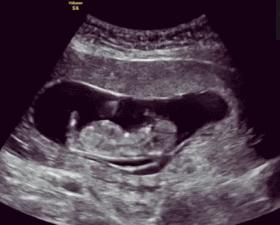

吃冰激凌时胎儿有什么感觉?

看过上面的内容,大家可能会有这样的感觉。吃冰激凌过量的影响,大部分都在妈妈身上,难道对胎宝宝就没有什么影响吗?当然有!当孕妈妈吃冰激凌时,宝宝也许也在品尝呢!

1、 胎儿喜欢甜味

怀着二宝去做四维彩超,好不容易排到了,躺下检查,医生却告诉我:“胎宝宝一直不肯翻身。你不如吃块巧克力,让他高兴高兴。”我们都知道,胎宝宝四个月就能通过羊水品尝到妈妈吃到的食物味道,而且他们都很喜欢甜食。所以表妹肚子里的小宝宝,才会因为一口冰激凌拼命折腾,高兴得手舞足蹈。